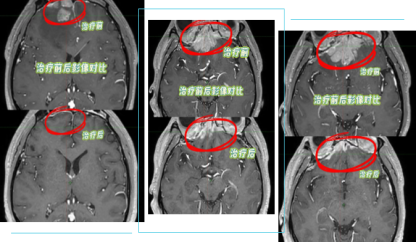

经过20次精准放疗,复查结果令人振奋:颅内侵犯肿瘤基本消退,脑水肿大幅减轻,疼痛与出血症状完全消失,几乎实现“临床清零”,治疗效果远超预期。这场从颅内转移走向临床清零的生命奇迹,只是济南君心肿瘤医院守护生命的又一个开始。